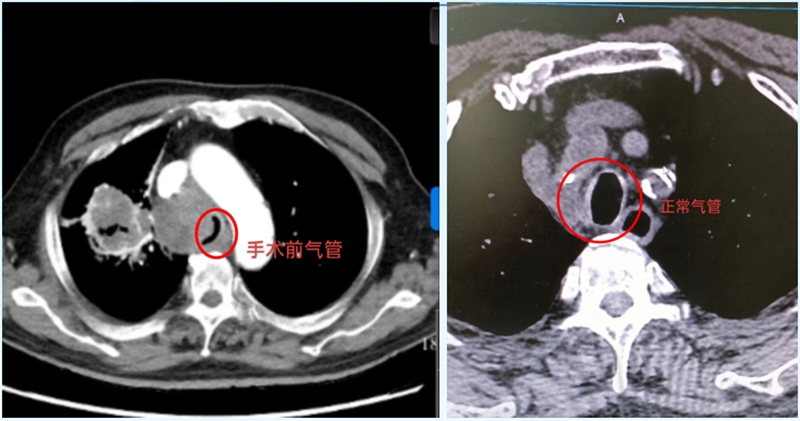

CT影像揭開(kāi)了兇險(xiǎn):右肺門(mén)區(qū)的惡性腫瘤已悄然“逼近”氣道,把氣管擠得只剩一條窄縫?!熬拖裼檬制×瞬弊樱瑲飧疚贿M(jìn)去!”醫(yī)生快速判斷,立即展開(kāi)抗炎、平喘治療,暫時(shí)為于大爺“松了綁”??烧l(shuí)也沒(méi)想到,這場(chǎng)“呼吸保衛(wèi)戰(zhàn)”才剛剛開(kāi)始。

次日凌晨,于大爺?shù)暮粑蝗辉俅巍案婕薄?。監(jiān)護(hù)儀上的血氧飽和度直線下降,他張著嘴卻發(fā)不出聲音,仿佛有只無(wú)形的手死死扼住喉嚨。呼吸內(nèi)鏡中心主任劉傳偉聞?dòng)嵹s來(lái),盯著影像片眉頭緊鎖:“腫瘤壓迫氣管成了‘細(xì)線’,必須立刻撐開(kāi)氣道,否有生命危險(xiǎn)!

支氣管鏡鏡頭下,氣道中下段被瘤體壓得只剩發(fā)絲寬,粘痰像“絆腳石”堵在狹窄處。劉傳偉主任穩(wěn)住鏡身,助手精準(zhǔn)遞過(guò)支架推送器——“3、2、1,釋放!”隨著“咔嗒”一聲輕響,支架如“微型橋梁”撐開(kāi)塌陷的氣管。

如今,于大爺已能正常吃飯、散步,后續(xù)抗腫瘤治療正在穩(wěn)步推進(jìn)。這枚11厘米長(zhǎng)的L型支架,不僅是醫(yī)生用專(zhuān)業(yè)與速度編織的“呼吸通道”,更藏著醫(yī)者對(duì)生命的敬畏:“哪怕只有1%的希望,我們也要拼盡全力。”